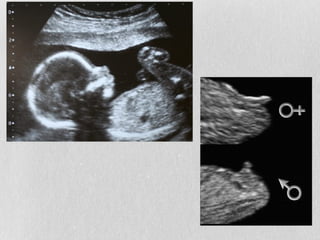

O documento discute os tipos de aconselhamento genético oferecidos quando problemas genéticos são detectados nos pais ou no feto antes ou durante a gravidez, incluindo as principais indicações e técnicas como amniocentese, cariotipagem e ultrassonografia para diagnóstico pré e pós-natal de alterações genéticas.